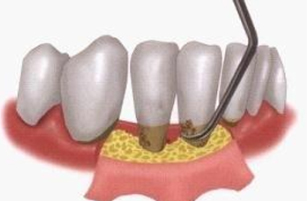

01:定期潔牙去除牙結石和牙菌斑等有(yǒu)害物(wù)質(zhì),使牙龈炎症消退 02:龈下刮治把牙龈下方的牙結石、龈下菌斑和牙周袋裏的炎性肉芽組織清除

02:龈下刮治把牙龈下方的牙結石、龈下菌斑和牙周袋裏的炎性肉芽組織清除 03:牙周翻瓣術用(yòng)手術的方法将牙龈切開翻瓣,使病損暴露後再清除結石、菌斑等